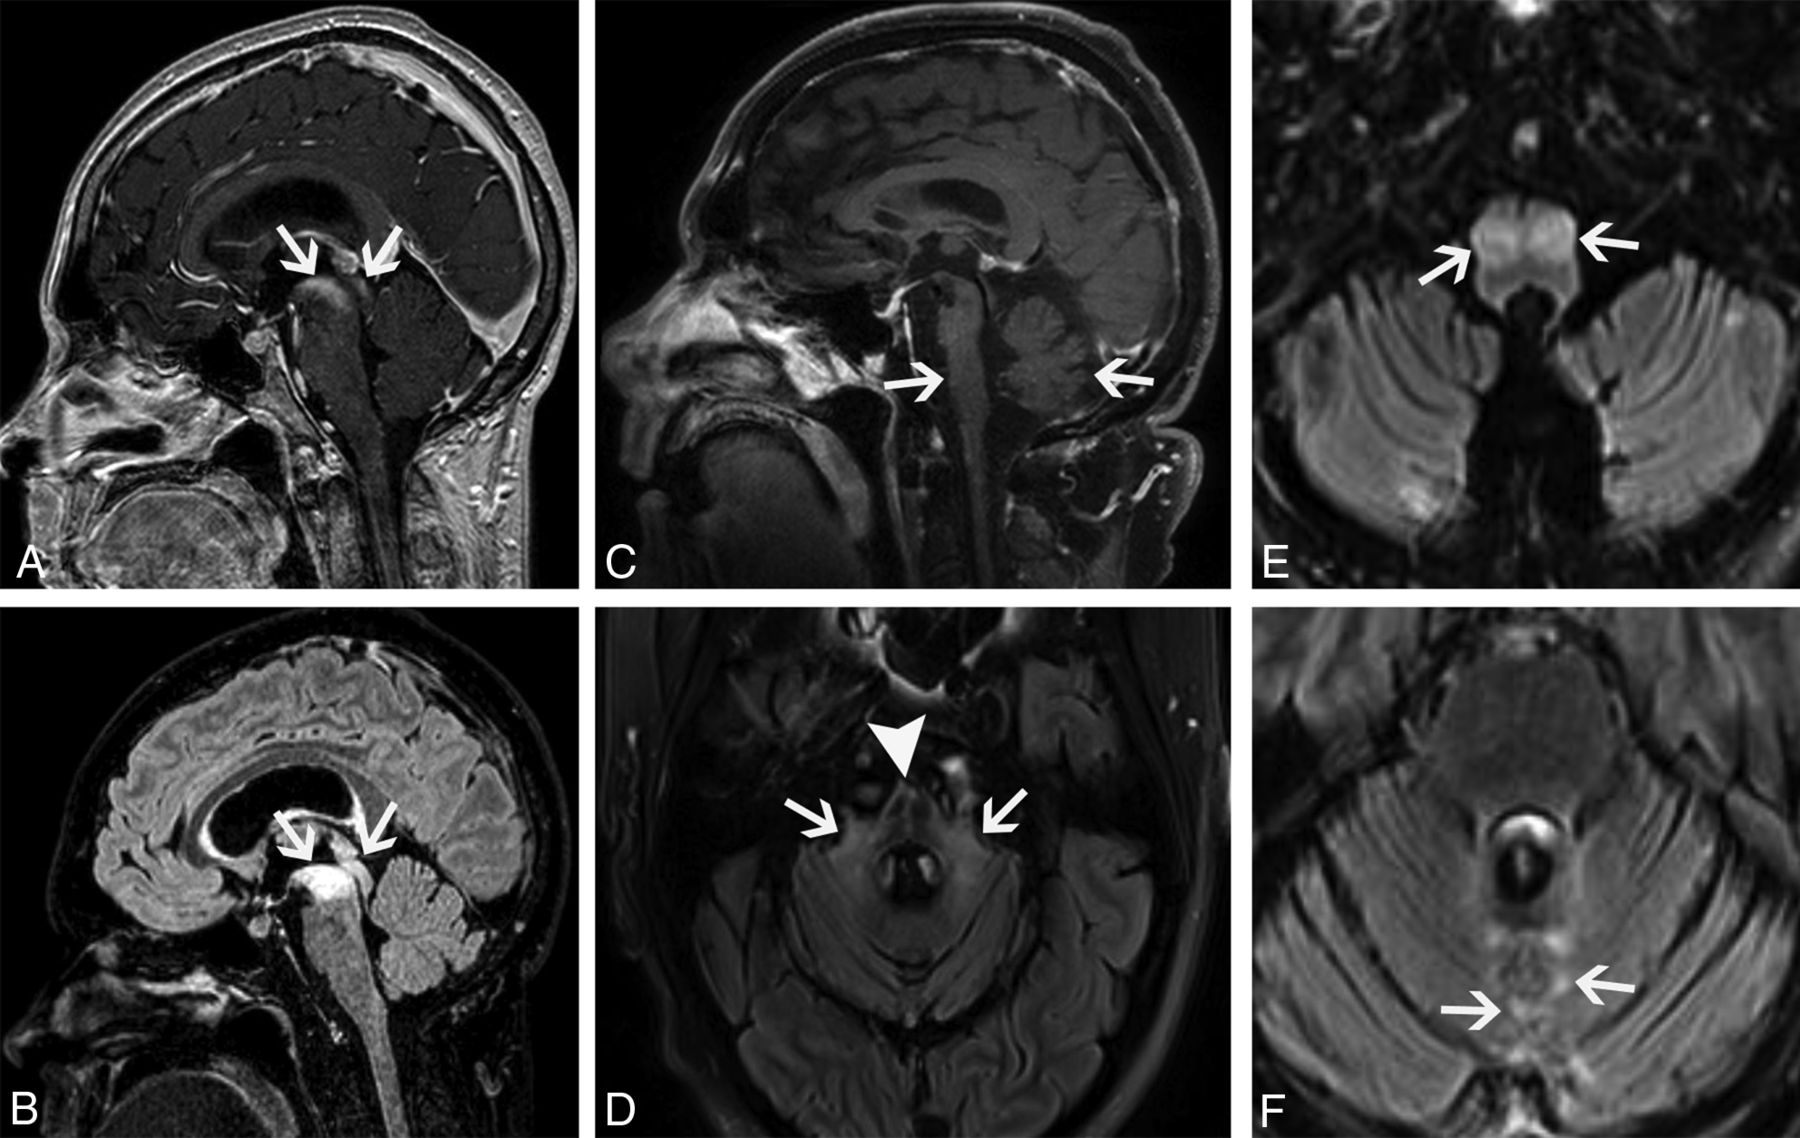

Classic limbic encephalitis (A and B). A 75-year-old healthy man presented with abrupt onset of memory loss and staring spells over several days. CSF analysis was positive for LGI1 autoantibodies. FDG-PET/CT axial image (A) shows marked hypermetabolism in the bilateral mesial temporal lobes (A, arrows). Axial double inversion recovery MR imaging image (B) shows corresponding increased T2 signal in both mesial temporal lobes (B, arrows). Atypical limbic encephalitis (C–F). A 29-year-old man with a history of resected nongerm cell testicular cancer presented months after treatment with worsening memory, diminished executive function, hypogonadism, and hypothyroidism. CSF analysis showed increased total protein but was otherwise normal. Axial FLAIR (C) and coronal T1-weighted postcontrast (D) images show abnormal T2 signal in the hypothalamus (C, arrows) and enhancement of the mammillary bodies (D, arrows). He was diagnosed with paraneoplastic limbic encephalitis with atypical involvement of the hypothalamus and mammillary bodies. He opted for observation with symptomatic improvement over months. Follow-up MR imaging shows improved mild residual hypothalamic T2 signal (E, arrows) and decreased enhancement of the mammillary bodies (F, arrows).

Limbic encephalitis mimicking a tumor. A 31-year-old man presented after being found unconscious while doing repair work on his home. He had multiple neurologic symptoms, including impaired thermoregulation, hypersexuality, and depression. Axial FLAIR (A) and coronal T1-weighted postgadolinium (B) images show extensive increased T2 signal and masslike enhancement centered in the region of the hypothalamus (A and B, arrows). The findings were initially considered worrisome for a neoplastic process, such as lymphoma, versus an inflammatory lesion, such as lymphocytic hypophysitis. Biopsy of this region showed a nonspecific macrophage-rich demyelinating lesion with no evidence of tumor. He was later found to have anti-Ma2 serum positivity and a mediastinal germ cell tumor. Images of the brain from his staging FDG-PET/CT show asymmetric FDG uptake in the left mesial temporal lobe (C, arrows), separate from the affected regions on his MR imaging. He was treated with chemotherapy and high-dose corticosteroids with gradual improvement in his symptoms. Axial FLAIR (D) and coronal postgadolinium (E) MR imaging obtained 1 year later show marked improvement in the prior findings, with mild residual hypothalamic T2 signal (D, arrows) and mild enhancement of the tuber cinereum (E, arrows). His subsequent FDG-PET/CT shows decreased FDG avidity in the previously involved left mesial temporal lobe (F, arrows). Ultimately, his intracranial findings were consistent with limbic encephalitis rather than malignancy.